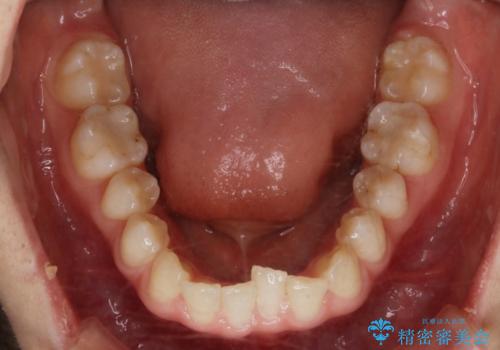

- 上下前歯のがたつきが気になるとご相談にいらした方です。

一見前歯のがたつきだけ改善させれば良い様に見えますが、このがたつきの原因は奥歯の嚙み合わせのズレからくるものであったため、インビザラインFULLで噛み合わせの改善から行っていきました。前歯の角度も改善されたために頑張って唇を閉じる必要がなくなり、横顔のシルエットも綺麗になりました。

前歯のがたつきだけを治そうとした場合、噛み合わせは二の次なってしまう事が多く、せっかく綺麗になった歯並びも後戻りしやすくなります。奥歯の噛み合わせからしっかり機能させることで、長期間にわたって綺麗な歯並びを保ちやすくなります。